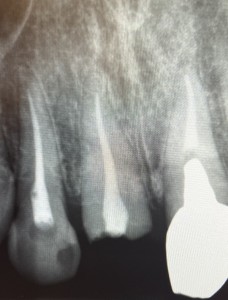

診察をしたところ、右上の差し歯は被せ物と一緒に歯が折れていましたが、幸いにも、歯根が割れていないことがわかりました。外れた差し歯の隣もすでに神経がなく、灰色に変色していました。患者様は、これを機に、右上2本を被せなおしたいとのご希望でした。

2日目〜5日目 右上1番の根管治療を行い、土台を立てました。

6日目〜7日目 右上2番の根管治療を行い、土台を立てました。